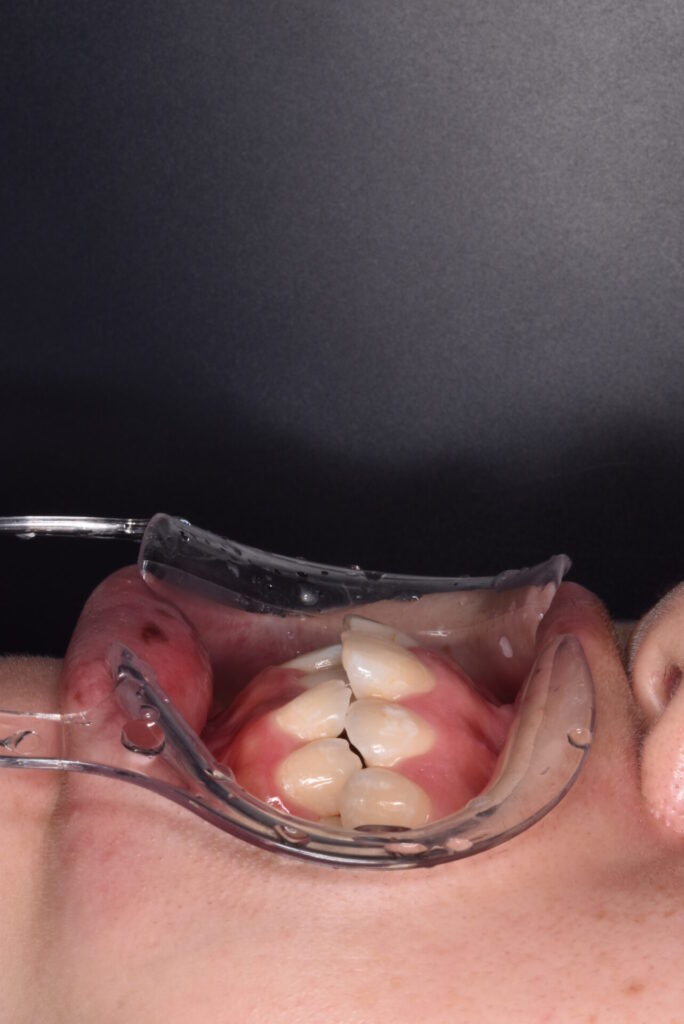

矯正後

矯正はインビザライン モデレートで行っています。追加アライナーなし 途中妊娠出産のため来院間隔が空いています。